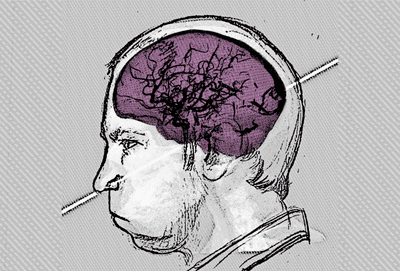

According to the authors of a new study, recreating the beam’s path through Bugorski’s skull was particularly challenging due to a lack of original images or medical documents. All they had to go on was a single, grainy photograph showing the approximate course of the ray through the physicist’s swollen head.

When creating a 3D rendering of the image, however, the authors noticed that the original photo is somewhat deceptive, as it appears to be a profile shot when in fact it depicts a slight rotation of Bugorski’s face. This enabled them to reconstruct the line of damage, which passes mostly through Bugorski’s temporal lobe, close to the point at which it meets the occipital lobe.

This, say the researchers, probably explains why the Soviet scientist began experiencing epileptic seizures following the accident.

The reconstructed proton beam trajectory also crosses the bony labyrinth of Bugorski’s left ear, which makes sense given that he became deaf on this side after the incident. He also experienced numbness on the left side of his face, which the researchers say may be due to the beam damaging either the infraorbital nerve or the temporal bone, before exiting near his left nostril.

“It is noteworthy that, despite the injury occurring in a region associated with language (heard, spoken, and read) in the temporal lobe, and at the boundary with the occipital lobe, related to vision, the accident, apart from the expected fatigue, appears not to have significantly impaired Bugorski’s perception or intellectual faculties,” write the authors.